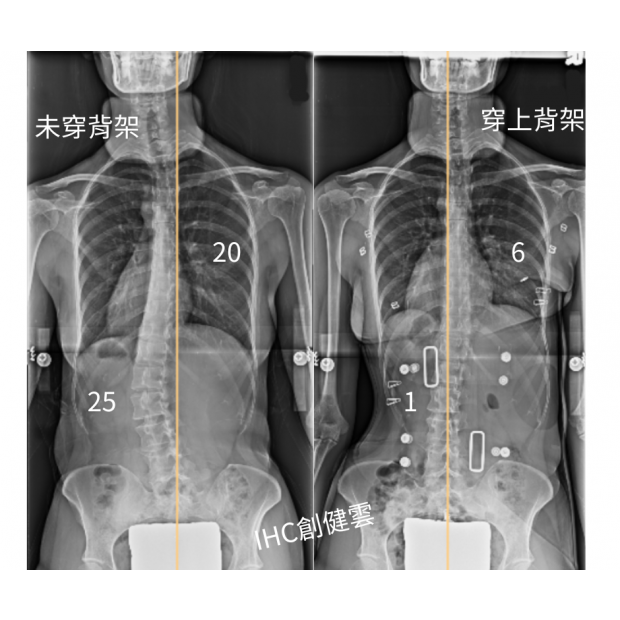

33歲脊椎側彎成年女性,胸彎20度,腰彎25度

33歲脊椎側彎成年女性,胸彎20度,腰彎25度 穿上背架後立即矯正效果優異